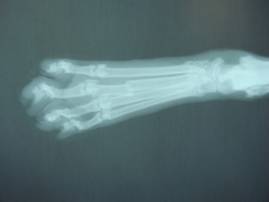

レントゲン検査にて、

右後肢第三中足骨が骨折していることがわかりました。

(右後ろ脚、中指にあたる部分の足の甲)

43-03